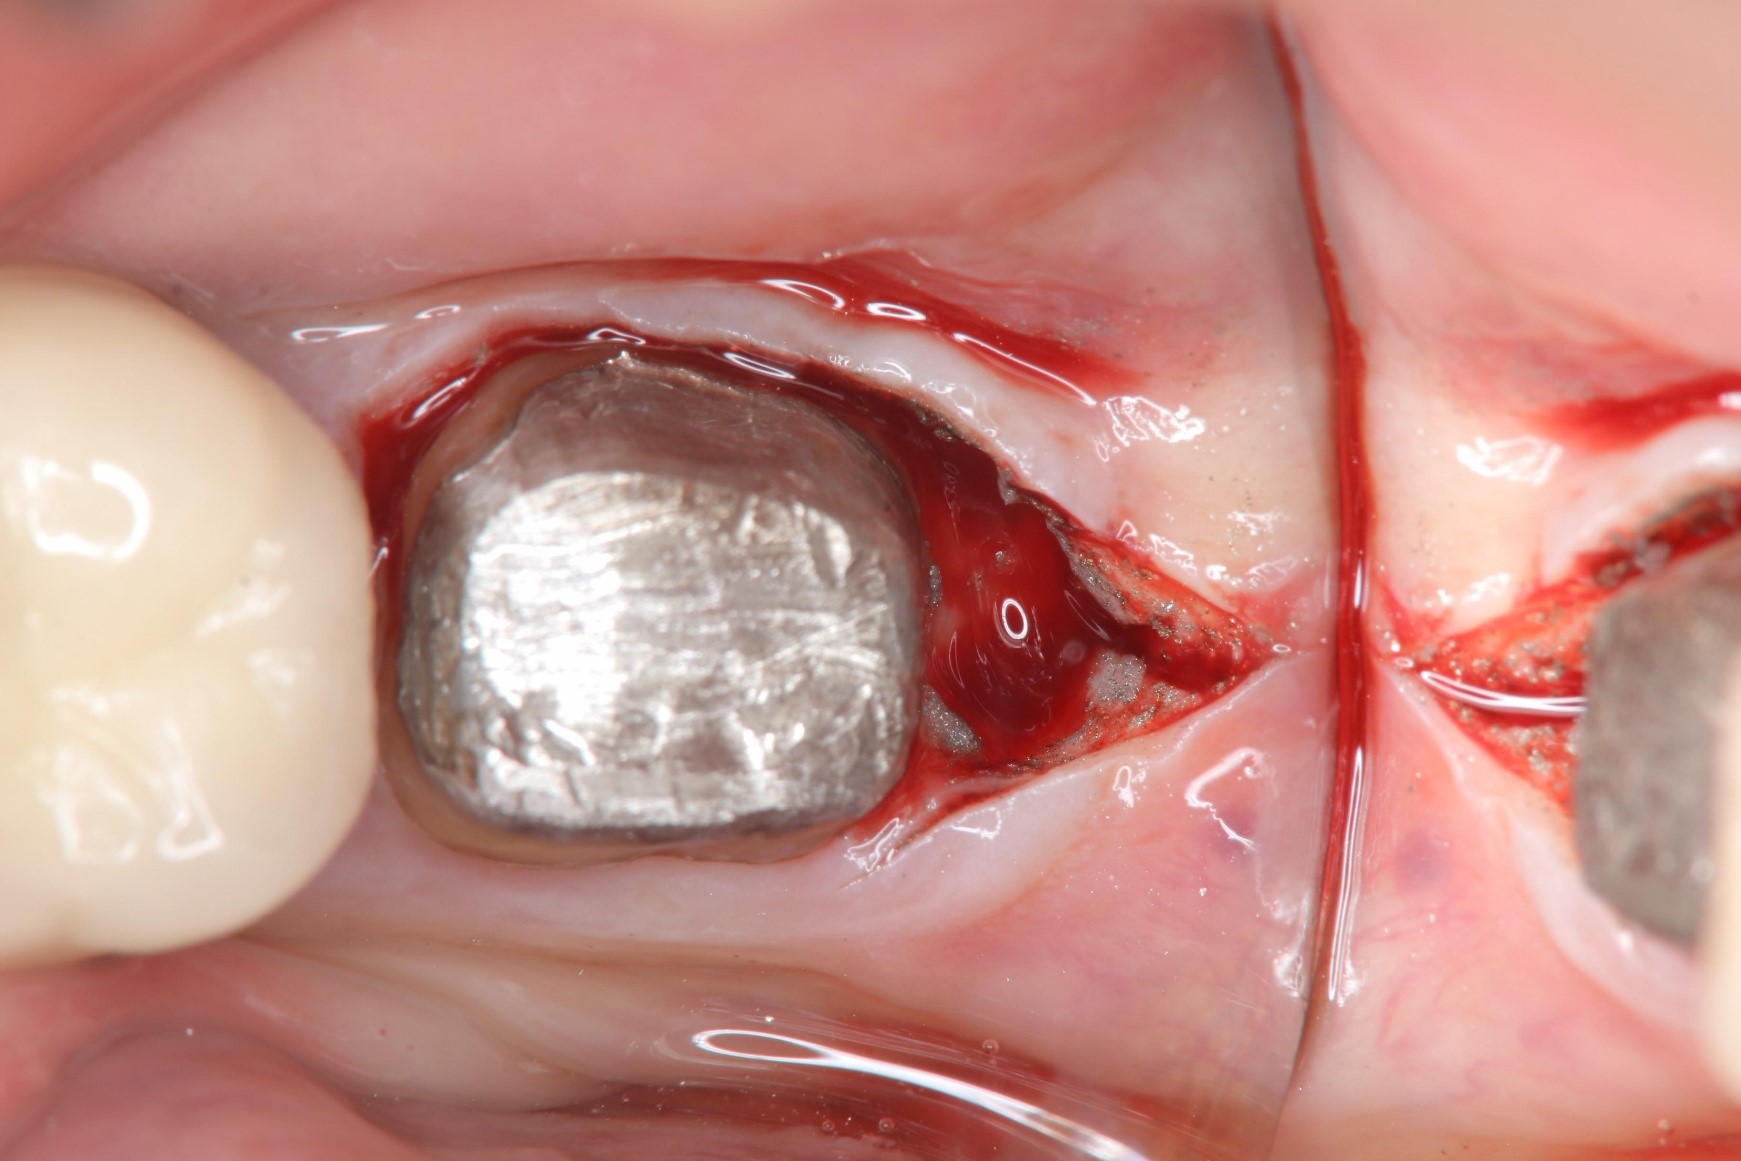

牙冠增長手術